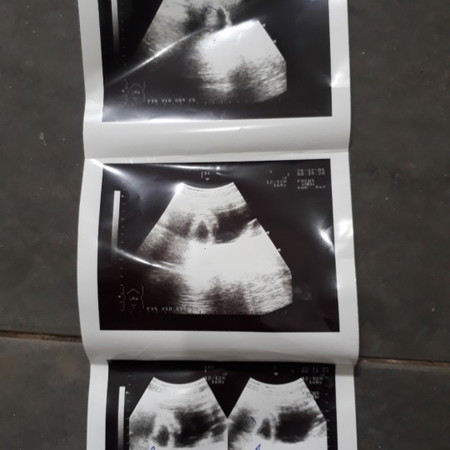

แม่ๆมีใครซาวเจอตัวเด้กเกิน2เดือนไหมค่ะของเรา2เดือนยังไม่เห้นเลยแต่ที่หมอวงไว้คิดว่าน่าจะเป็นเด้กแต่ตัวเล้กมากขอคำแนะนำหน่อยค่ะ

เป็นไปได้ว่า อายุครรภ์อาจจะน้อยกว่าที่นับ เพราะไข่อาจจะตกช้ากว่ากำหนด ตัวอ่อนยังเล็กมากอยู่ จึงยังไม่พบ ก็เป็นได้ค่ะแม่ ทานโฟลิคทุกวัน พักผ่อนเยอะๆ นะคะ ซาวด์ครั้งหน้าอาจจะได้เจอกันแล้วจ้า

ของเราเจอตอน 6สัปดาห์ 1 วันเองค่ะ (ประมาณเดือนกว่า) เจอแล้วค่ะ ตะมุตะมิมาก😂😂

น้องอาจจะยังตัวเล็กอยู่นะคะ หมอนัดอีกเดี๋ยวเค้าก็ซาวอีกค่ะ